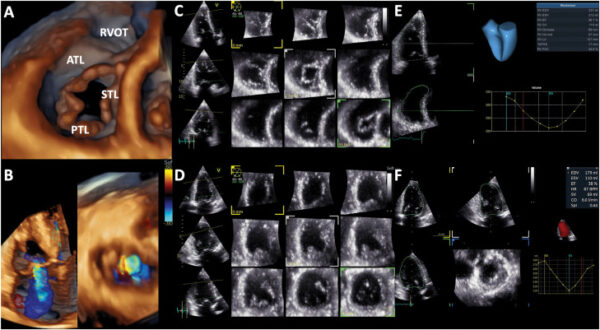

The April JASE issue is now online and features an Original Investigation “Invasive Validation of Right Ventricular Stroke Volume and Tricuspid Regurgitant Volume Obtained from Three-Dimensional Echocardiography.” Regarding this paper, author Luigi Badano, MD, PhD, FESC, FASE, remarked, “Quantifying the severity of tricuspid regurgitation is essential given its

significant implications for prognosis and management. Conventional Doppler quantification methods are inadequate because they rely on geometric and fluid-dynamic assumptions and overlook intrabeat variability in regurgitant flow. The three-dimensional volumetric method is a superior alternative, providing a reliable measurement of regurgitant volume independent of geometric, fluid-dynamic, or temporal assumptions. This method is crucial for applications following transcatheter interventions, where Doppler techniques are not suitable.”